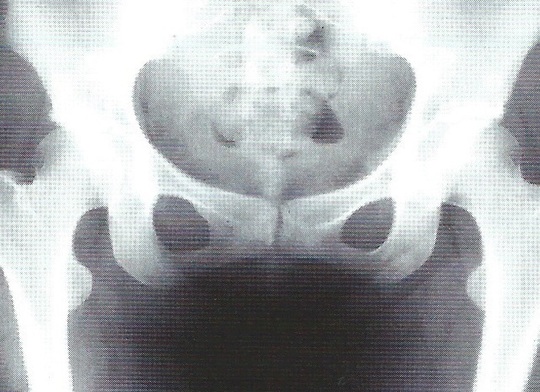

【診断】

問診、股関節の誘発痛可動域制限、X線像などで判断します。

正常股関節